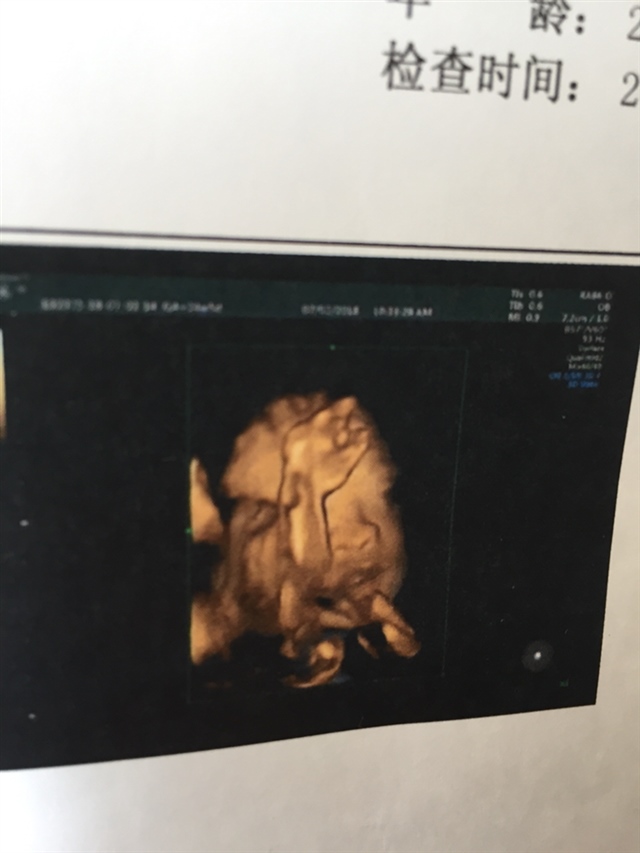

孕20周+6天

接四维顺利通过